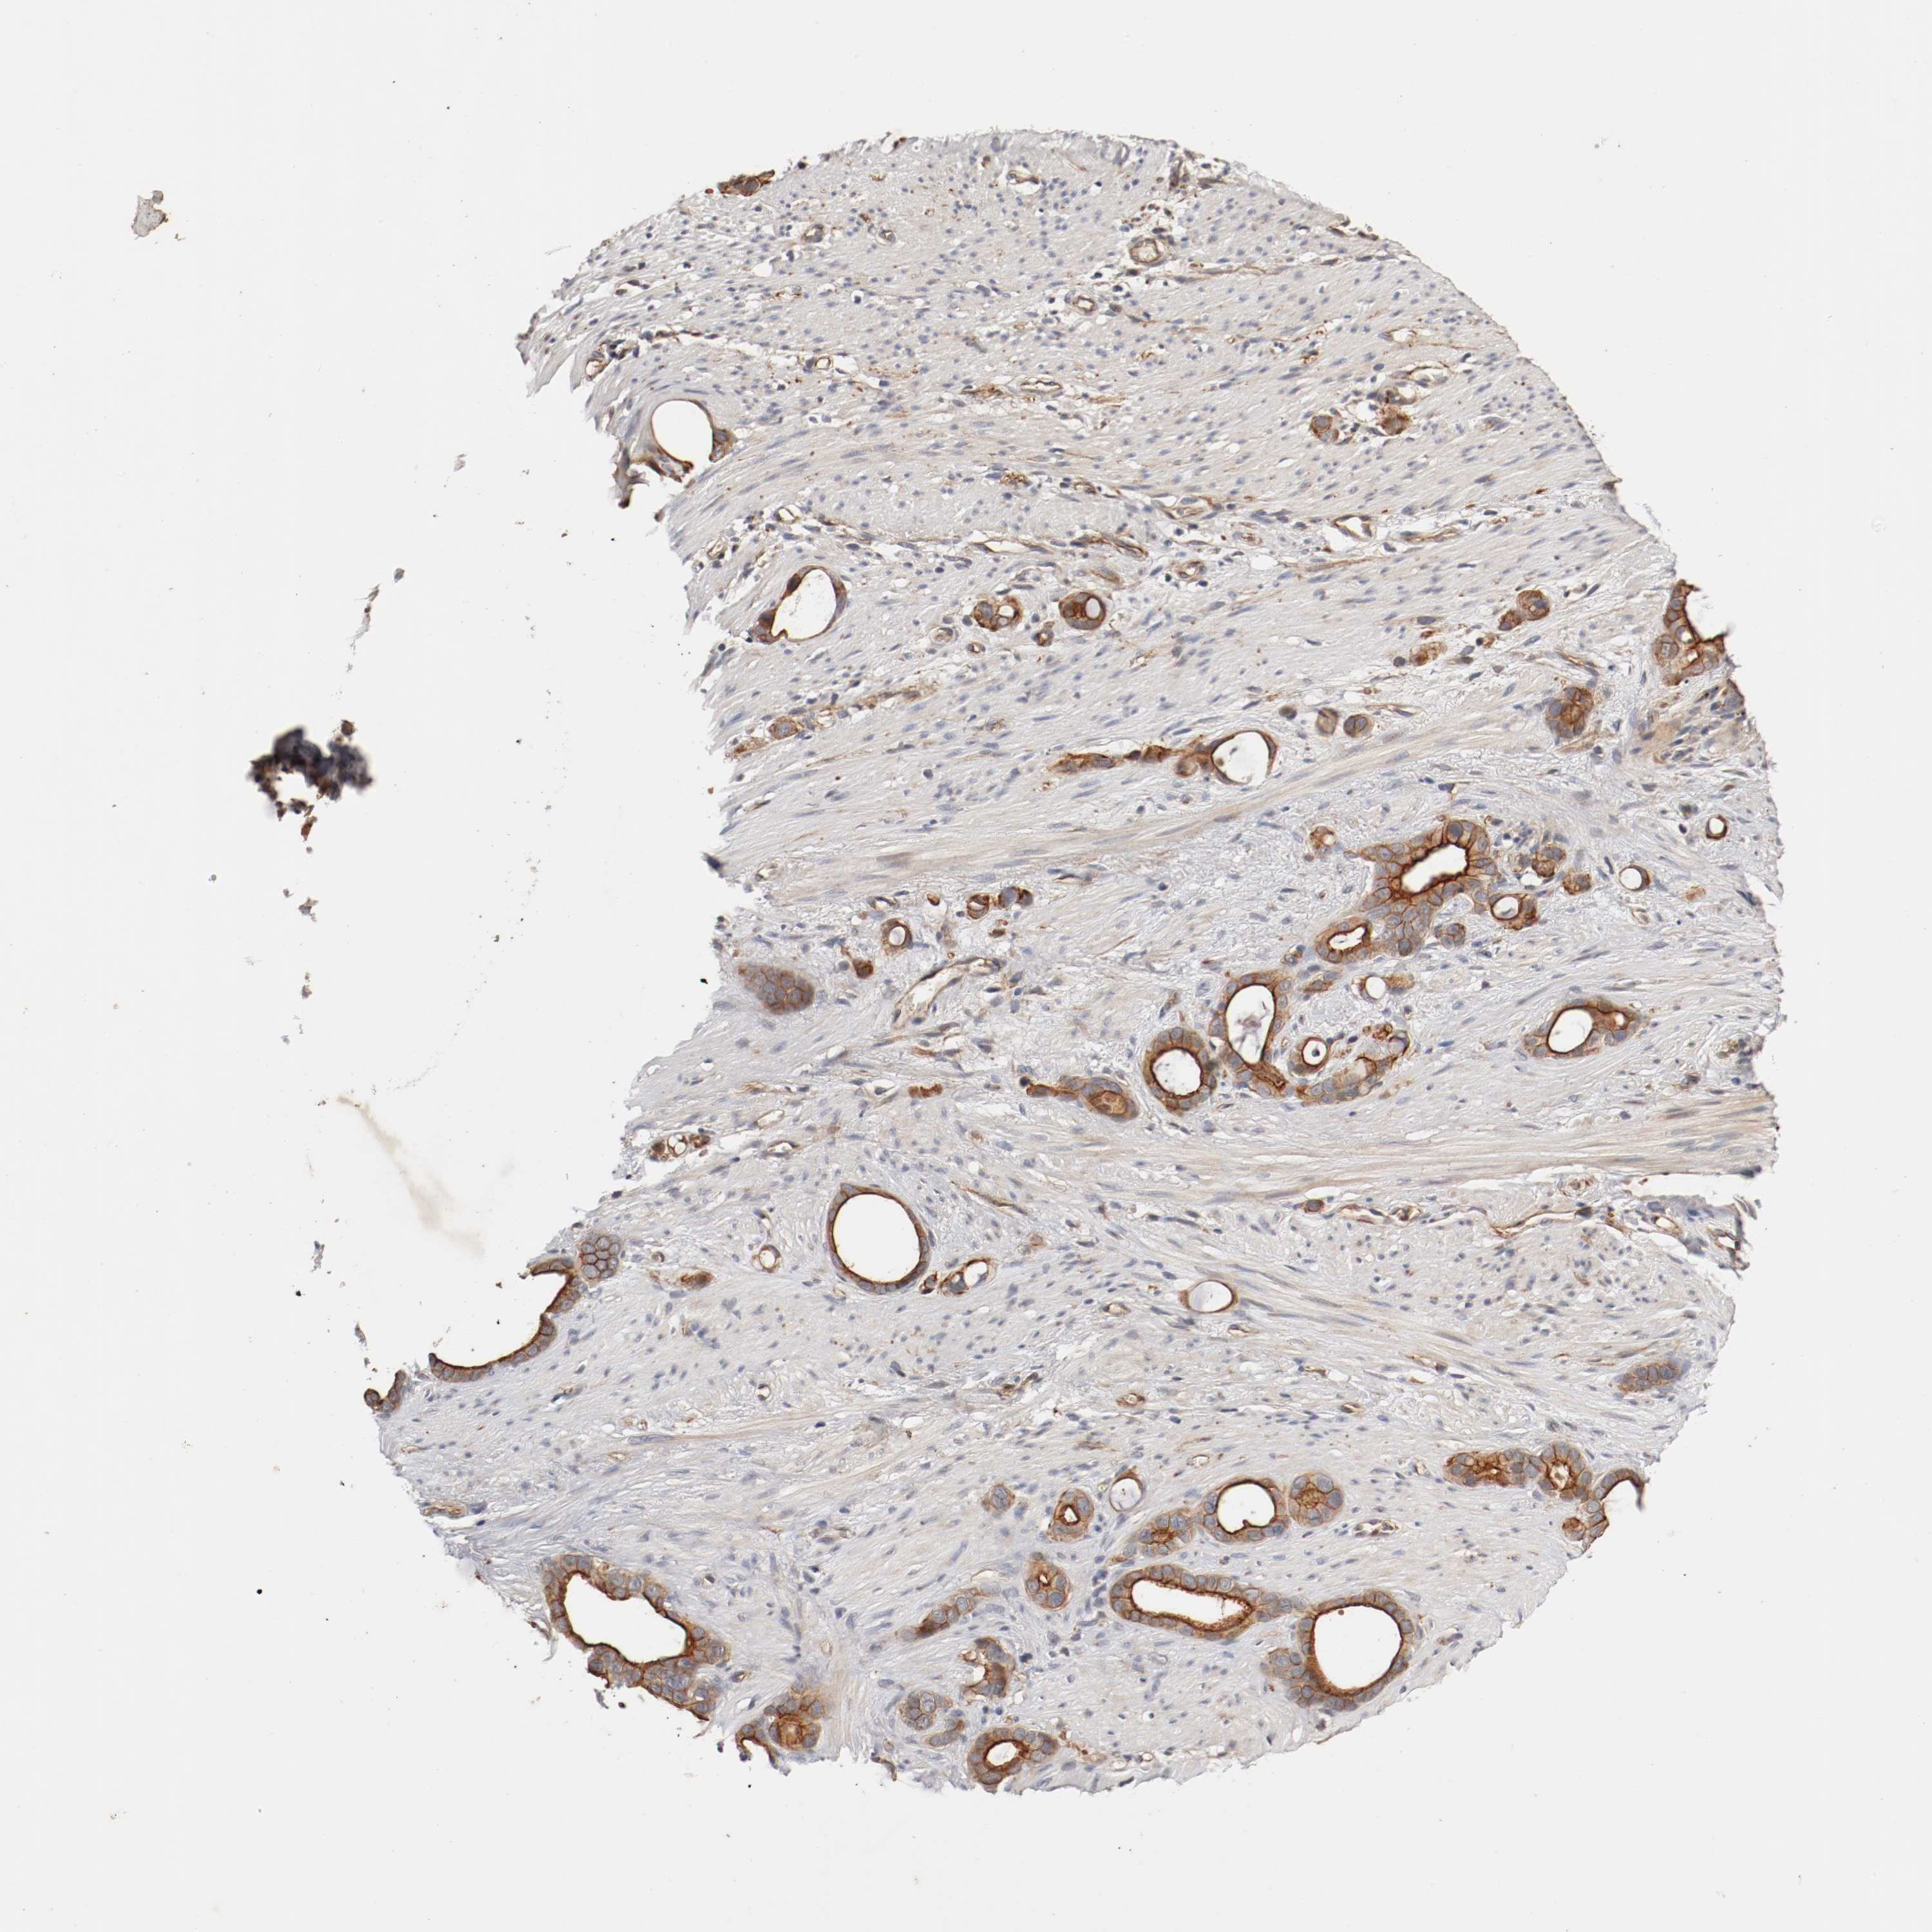

STOMACH CANCER - Protein expressioni

A mouse-over function shows sample information and annotation data. Click on an image to view it in a full screen mode. Samples can be filtered based on level of antibody staining by selecting one or several of the following categories: high, medium, low and not detected. The assay and annotation is described here.

Antibody stainingi

Antibody staining in the annotated cell types in the current human tissue is reported as not detected, low, medium, or high, based on conventional immunohistochemistry profiling in selected tissues. This score is based on the combination of the staining intensity and fraction of stained cells.

Each image is clickable and will lead to virtual microscopy that enables deeper exploration of all samples and also displays staining intensity scores, fraction scores and subcellular localization as well as patient and tissue information for each sample.

Antibody HPA005157

Staining

High

Medium

Low

Not detected

Intensity

Strong

Moderate

Weak

Negative

Quantity

>75%

75%-25%

<25%

None

Location

Nuclear

Cytoplasmic/membranous

Cytoplasmic/membranous,nuclear

Adenocarcinoma, NOS

Adenocarcinoma, High grade